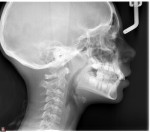

This is a 9yo girl with a high esthetic desire (wants to be a model/actor). She avulsed tooth #9 about 3 years ago, and she has been under treatment with other endodontists. I guess they attempted revascularization with MTA about year ago. #9 is ankylotic with a few mm’s infraposition. It is gray due to the MTA. #8 is slightly yellow/white due to calcification/obliteration but she says she feels cold testing and it is otherwise asymptomatic.

Then someone has to watch for her growth spurt – and as soon as it happens the tooth has to be removed – this will reduce the defect that will become much more on the growth of the maxilla – there is also some discussion about whether the ankylosed tooth will affect maxillary growth – this is much like placing an implant too early but worse. Orthodontic care for this potential movie star should also be delayed because any treatment now would have to be worked around this tooth and any eruptive force would created a vertical periodontal defect that might jeopardize the adjacent teeth.